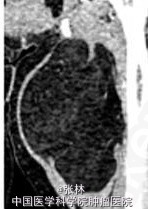

发现左大腿肿物1年,近来肿物明显增大。查体:大腿内侧见一肿物隆起,边界欠清,质中偏软,无明显搏动感,无压痛。

相当于股骨上段平面,大腿内侧肌群内见异常类圆形低密度影,边界清晰,边缘有中等密度线状分隔影伸向瘤内,增强后未见强化。

【诊断】脂肪瘤(病理确诊)。镜下见送检脂肪组织有大量成熟脂肪细胞,大小和形态不完全一致,瘤细胞排列紧密,并可见少量的纤维组织包被。

【讨论】 脂肪瘤(lipoma)是一种由成熟脂肪细胞构成的肿瘤,常有一薄层纤维包膜,呈扁平或分叶状,边缘清楚,包块质软。镜下见成熟的脂肪细胞堆积,其间有不规则纤维组织分隔。 本病发生于含有脂肪组织的全身任何部位,但多见于颈、肩、背、臀及肢体的皮下组织和腹膜后。亦可见于肠系膜、肾周、肌肉和筋膜下。皮下脂肪瘤发展缓慢,大小不一,大者可达10~20kg。表面皮色正常,包块质软。 影像诊断要点:X线表现为边缘规整、清晰的低密度区,而且随肌肉收缩其形态可发生变化。肿瘤越大,透光度相对越强。肿瘤内可发生不规则钙化。CT平扫肿瘤呈一个或多个边缘光整的极低密度区,多呈圆形或分叶状。周围组织受压。CT值约为-120~-80HU,密度均匀,有包膜,内部可有分隔。增强扫描无强化。脂肪瘤MRI信号具有特征性,呈短T1中长T2信号,在所有序列中均与皮下脂肪组织信号相同,边缘清楚,信号强度均匀,部分有低信号分隔。 脂肪瘤影像学表现有其特殊性,一般无须与其他病变鉴别。